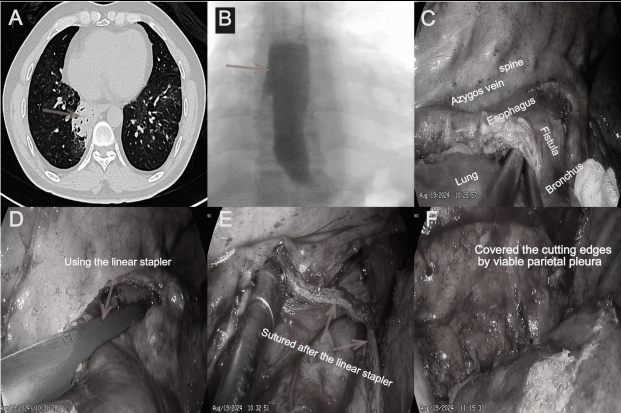

44岁的李先生,因反复呛咳2年余就诊,发现气管食管瘘导致右下肺实变不张,团队巧妙利用微创的手术方式,切除瘘道并创新性的使用胸膜覆盖瘘口切缘,成功避免的瘘道复发。这一创新性术式获得学术界高度认可,成功发表在胸外科专业SCI杂志上。

截止目前,已有近50余例获得性气管食管瘘的患者得到了有效的诊治。下一步,作为广州市特色项目,心胸外科将聚焦三大核心方向:一是建立获得性气管食管瘘的精准诊断体系,结合CT与内镜技术提升瘘口检出率;二是研发个体化修补方案,针对良恶性病例、不同瘘口大小制定差异化策略;三是推广微创技术规范,降低基层医院诊疗门槛。